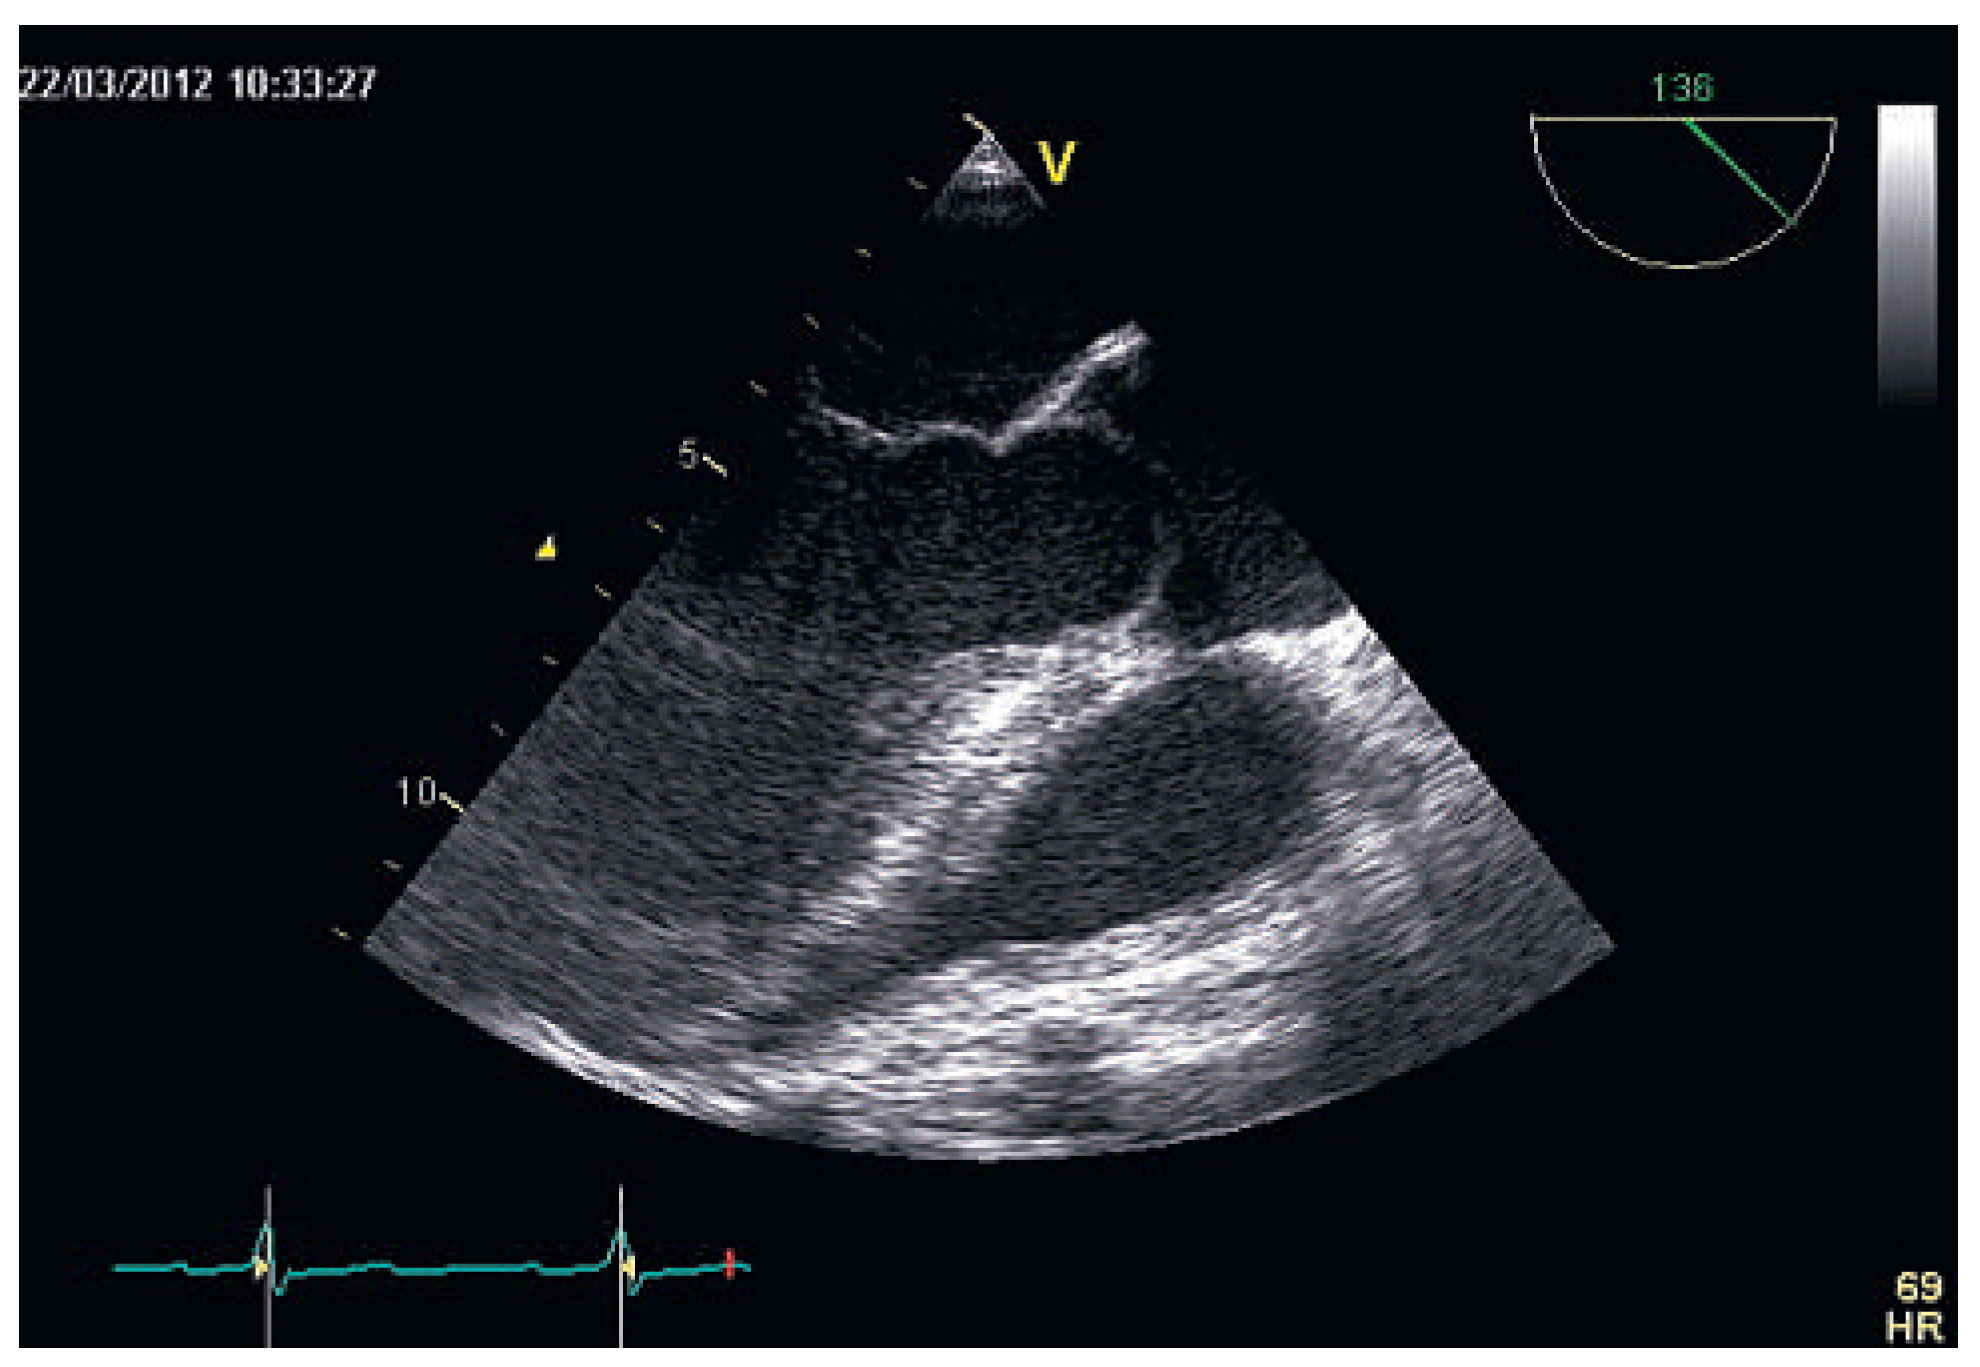

High Doppler-Derived Gradients Across the Aortic Valve May Be Misleading: Potential Causes of Valve Gradient Overestimation